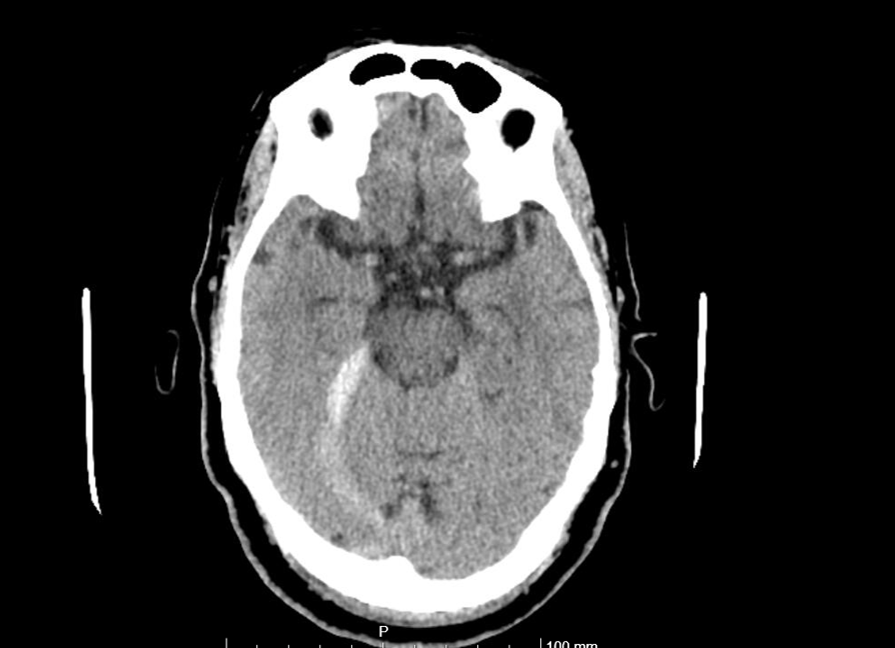

Pruebas de laboratorio normales. ECG con fibrilación auricular a 120 lpm. TAC craneal simple: Hemorragia subaracnoidea en tentorio derecho y hoz cerebral posterior junto con encefalopatía de pequeño vaso crónica severa (Fazekas 3).

Juicio clínico: Hemorragia subaracnoidea espontánea y otitis media crónica perforada en oído derecho.

A la anamnesis presentaba buen estado general salvo por la leve cefalea. Posteriormente presentó náuseas y empeoramiento general con aparición de fibrilación auricular rápida, vómitos y aumento de la cefalea. Fue vista por ORL con diagnóstico de otitis media crónica perforada en oído derecho. Posteriormente se realizó el TAC craneal que dio el diagnóstico final.